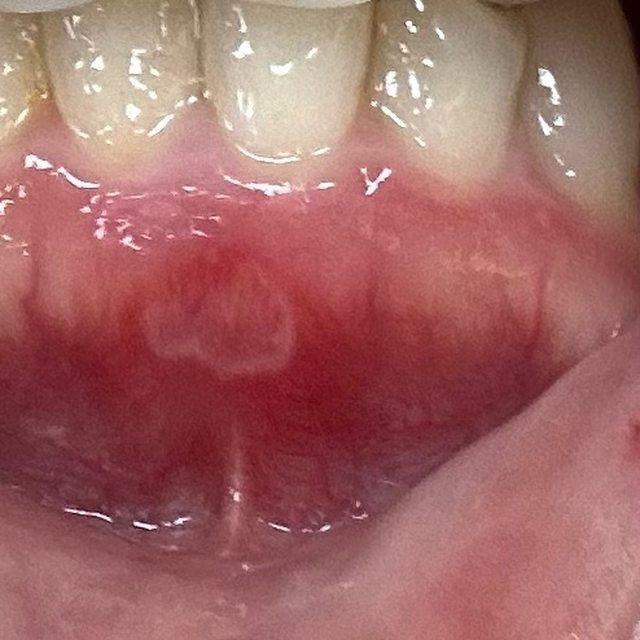

: 先來張嘴破圖:

: https://i.imgur.com/dK5XQGH.jpeg

: 破在下排牙齦處,這前期還好,不要看它沒有很白,它後期長大根本大魔王。它很會選位

: 置,這位置基本上不管做什麼事(吃飯、喝水、講話)都一定會碰到,我那個禮拜真的很

: 想死

: 它小時候我是用妥治安+口內膏。一般的痘痘有可能就消失了,但它很不一般,持續長大

: ,等他長到圖上那麼大,真的太痛,我真的沒勇氣繼續使用妥治安。